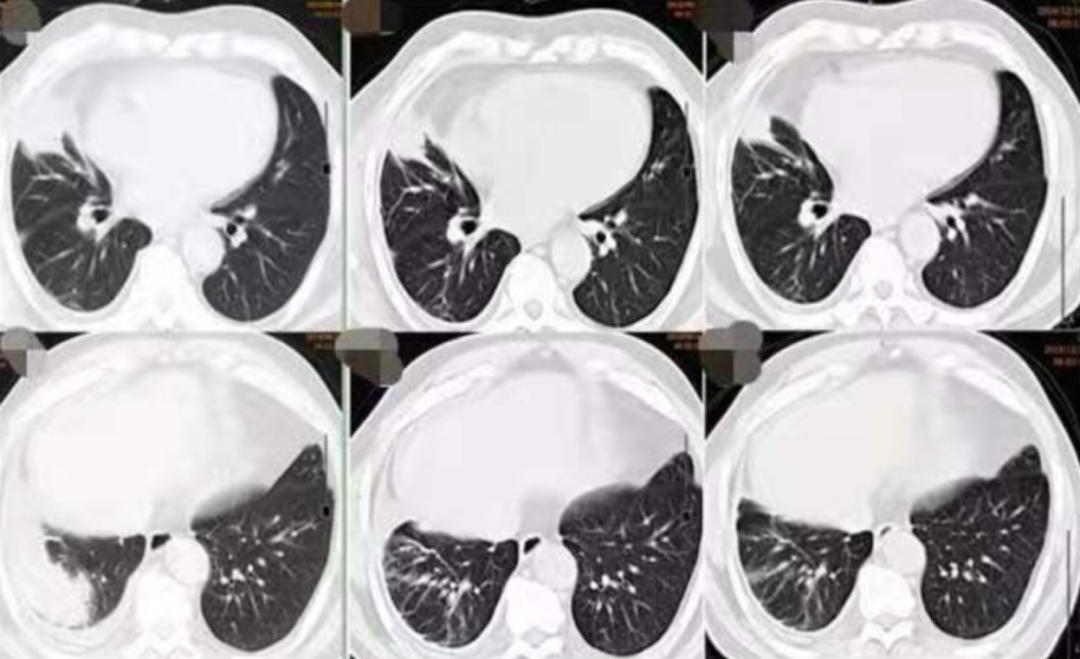

其影像学特点包括(图13):

(1)胸膜改变(早期即可出现):①胸膜斑:双侧胸壁中、下部对称性三角形阴影,部分有钙化;②胸膜增厚、粘连;③渗出性胸腔积液:双侧多见,可为血性。(2)肺部改变:①网状阴影(主要改变):中下肺细网、粗网、蜂窝状改变;②融合灶:双肺基底部,边界不清,范围不大的片状阴影;③肺门结构紊乱,密度增高,但无肺门淋巴结肿大。

图13:石绵肺的典型影像学表现(资料)

(从左至右)初诊、1月后、4月后:

图14:2019-09-16胸部CT(1月后):右肺中下叶团块、索条灶,右侧胸腔积液,较2019-08-14老片病灶略吸收,积液减少。2019-12-16胸部CT(4月后):右肺中下叶团块、索条灶,右侧胸腔积液,较2019-09-16老片病灶略吸收,积液减少。